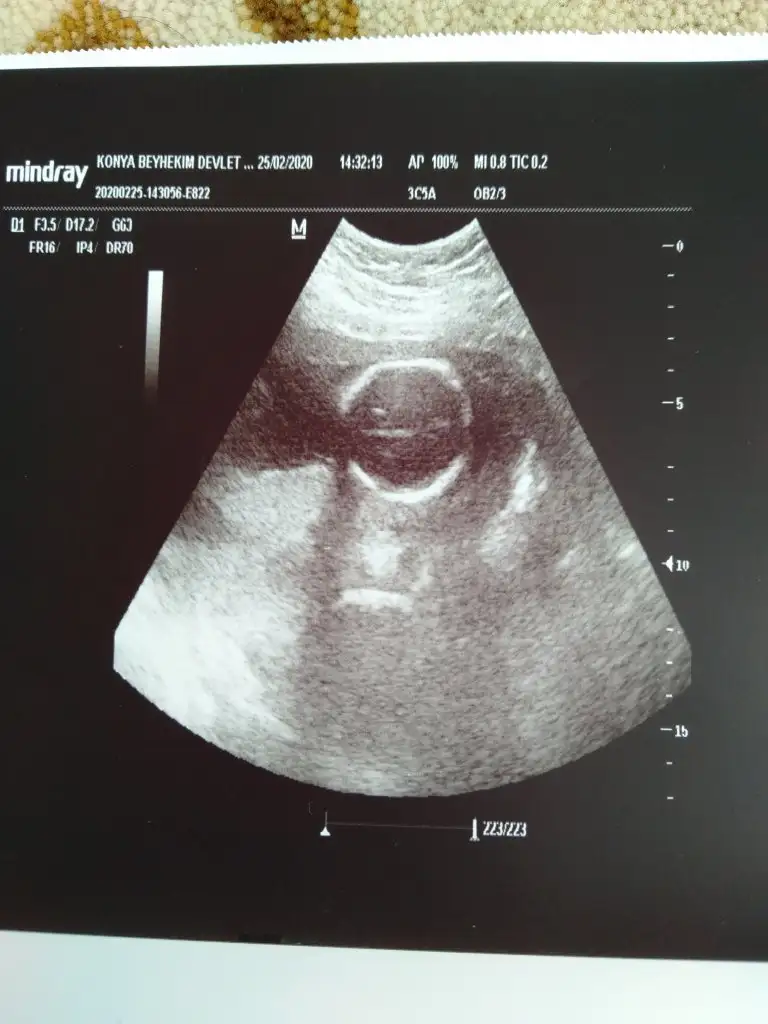

S.a Ikra meyra Ikra meyra cnm ultrason resmini alınca sana aticaktm bugüne kısmetmiş ben biseyy anlamadm ya görüntü net değil ya da ben tecrubesizim sana zahmet bakar msn sence cinsiyet ne bugün sırf cinsiyet için farkli doktora gittim 🤭☺️🤔

S.a Ikra meyra Ikra meyra cnm ultrason resmini alınca sana aticaktm bugüne kısmetmiş ben biseyy anlamadm ya görüntü net değil ya da ben tecrubesizim sana zahmet bakar msn sence cinsiyet ne bugün sırf cinsiyet için farkli doktora gittim 🤭🤔